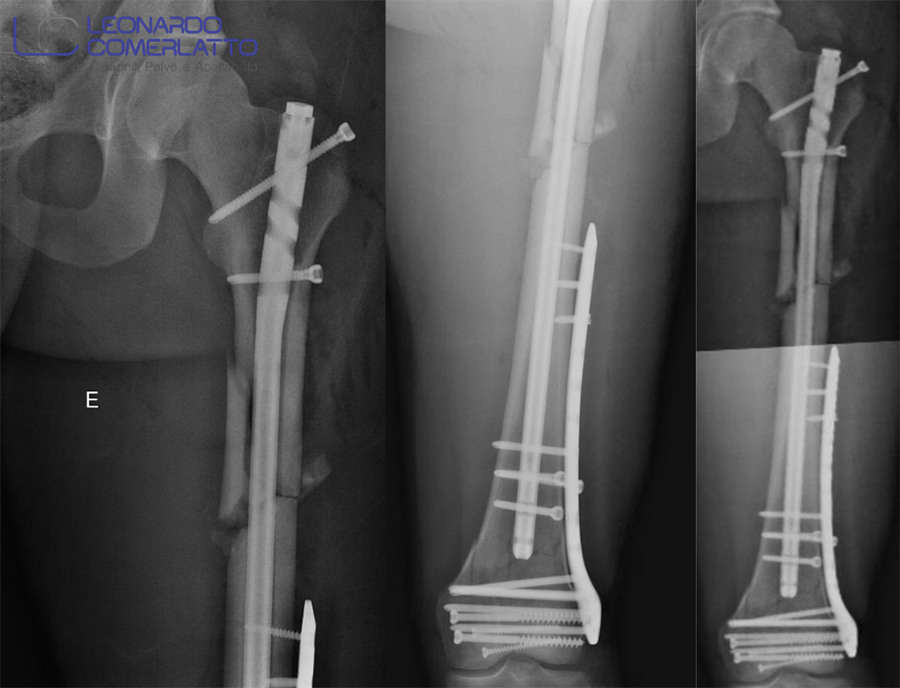

- Tratamento cirúrgico de uma fratura complexa e segmentar do fêmur, ocorrida em paciente jovem vítima de acidente de motocicleta. Os múltiplos componentes e gravidade de lesões como essa exigem detalhado planejamento e execução do procedimento por uma equipe especializada.